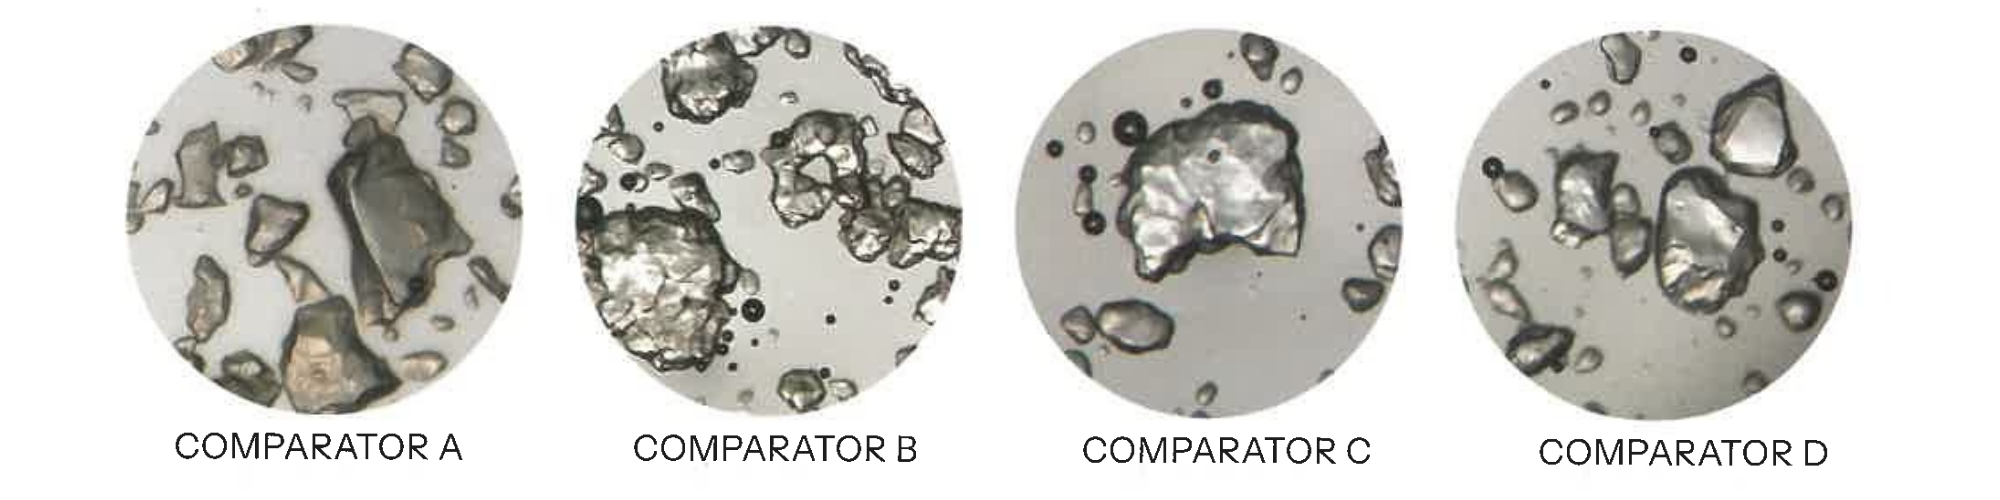

Wet Milling & Spherical Particle Formation

Revanesse® utilises a proprietary wet-milling process, an additional, time-intensive manufacturing step that refines HA into uniform, spherical particles.

Unlike irregular particle structures, spherical HA offers:

- Lower surface area → reduced inflammatory response

- Smoother gel consistency

- Enhanced tissue integration

- Greater predictability during placement

This process is fundamental to achieving subtle, controlled volumisation. The smooth, uniform particles promote better tissue integration and reduce the risk of a foreign-body reaction.